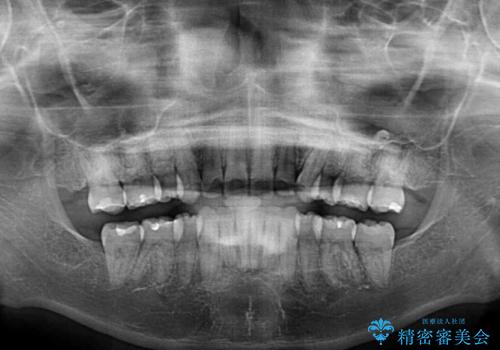

- 前歯のデコボコと上顎の前突感による口の閉じにくさを気にして来院された患者様です。

目立たない装置を希望されたので、上顎が裏側装置のハーフリンガルを選択し、上下左右の小臼歯(計4歯)を抜歯して矯正治療を行うこととしました。

治療期間の目安は2年半~3年間でしたが、咬み合わせにより上顎装置が頻繁に脱落してしまい、治療期間が長期化してしまいました。

期間はかかったものの、口元の張り出し感や歯のデコボコが解消され、患者様には大変満足していただけました。